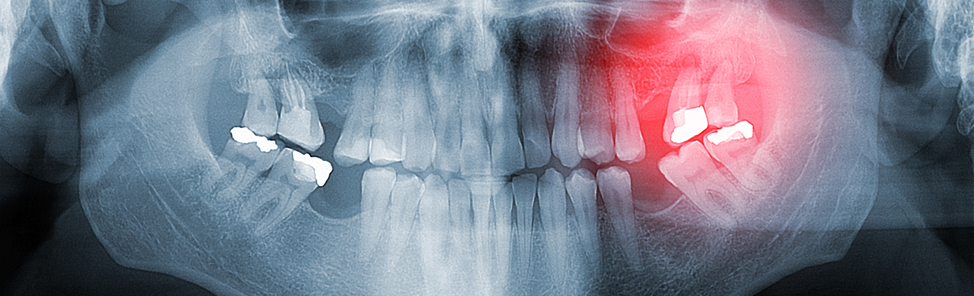

Chronisch-entzündliche Veränderungen des Zahnhalteapparates bezeichnet man als Parodontitis.

Druckempfindlichkeit, eine Rötung sowie eine erhöhte Blutungsneigung des Zahnfleisches können Anzeichen dafür sein. Mundgeruch und die Beeinträchtigung des Geschmacksinns können weitere Anhaltspunkte sein. Ist die Parodontitis schon weit fortgeschritten, führt dies zu einer Rückbildung des Zahnfleisches und schließlich zur Lockerung der Zähne.